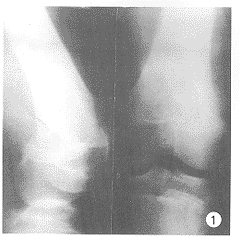

1.1 一般资料 5例病人中我院3例,辽宁中医院2例,均为男性,年龄13~41岁,平均24岁。病变部位及类型:TypeⅠ4例,其中大腿2例,前臂1例,盆腔1例;TypeⅡ1例,发生于左股骨。4/5就诊前有不同程度的外伤史。术前分别诊断为:大腿软组织肿瘤2例;盆腔肿瘤1例;股骨骨肉瘤1例(见附图);前臂筋膜间隙综合征1例,无一术前确诊。5例均为Ⅷ因子缺乏。

图1 14岁,男性,血友病假肿瘤(骨膜一型),骨周围软组织肿块影,有骨膜反应(术前误诊骨肉瘤)。